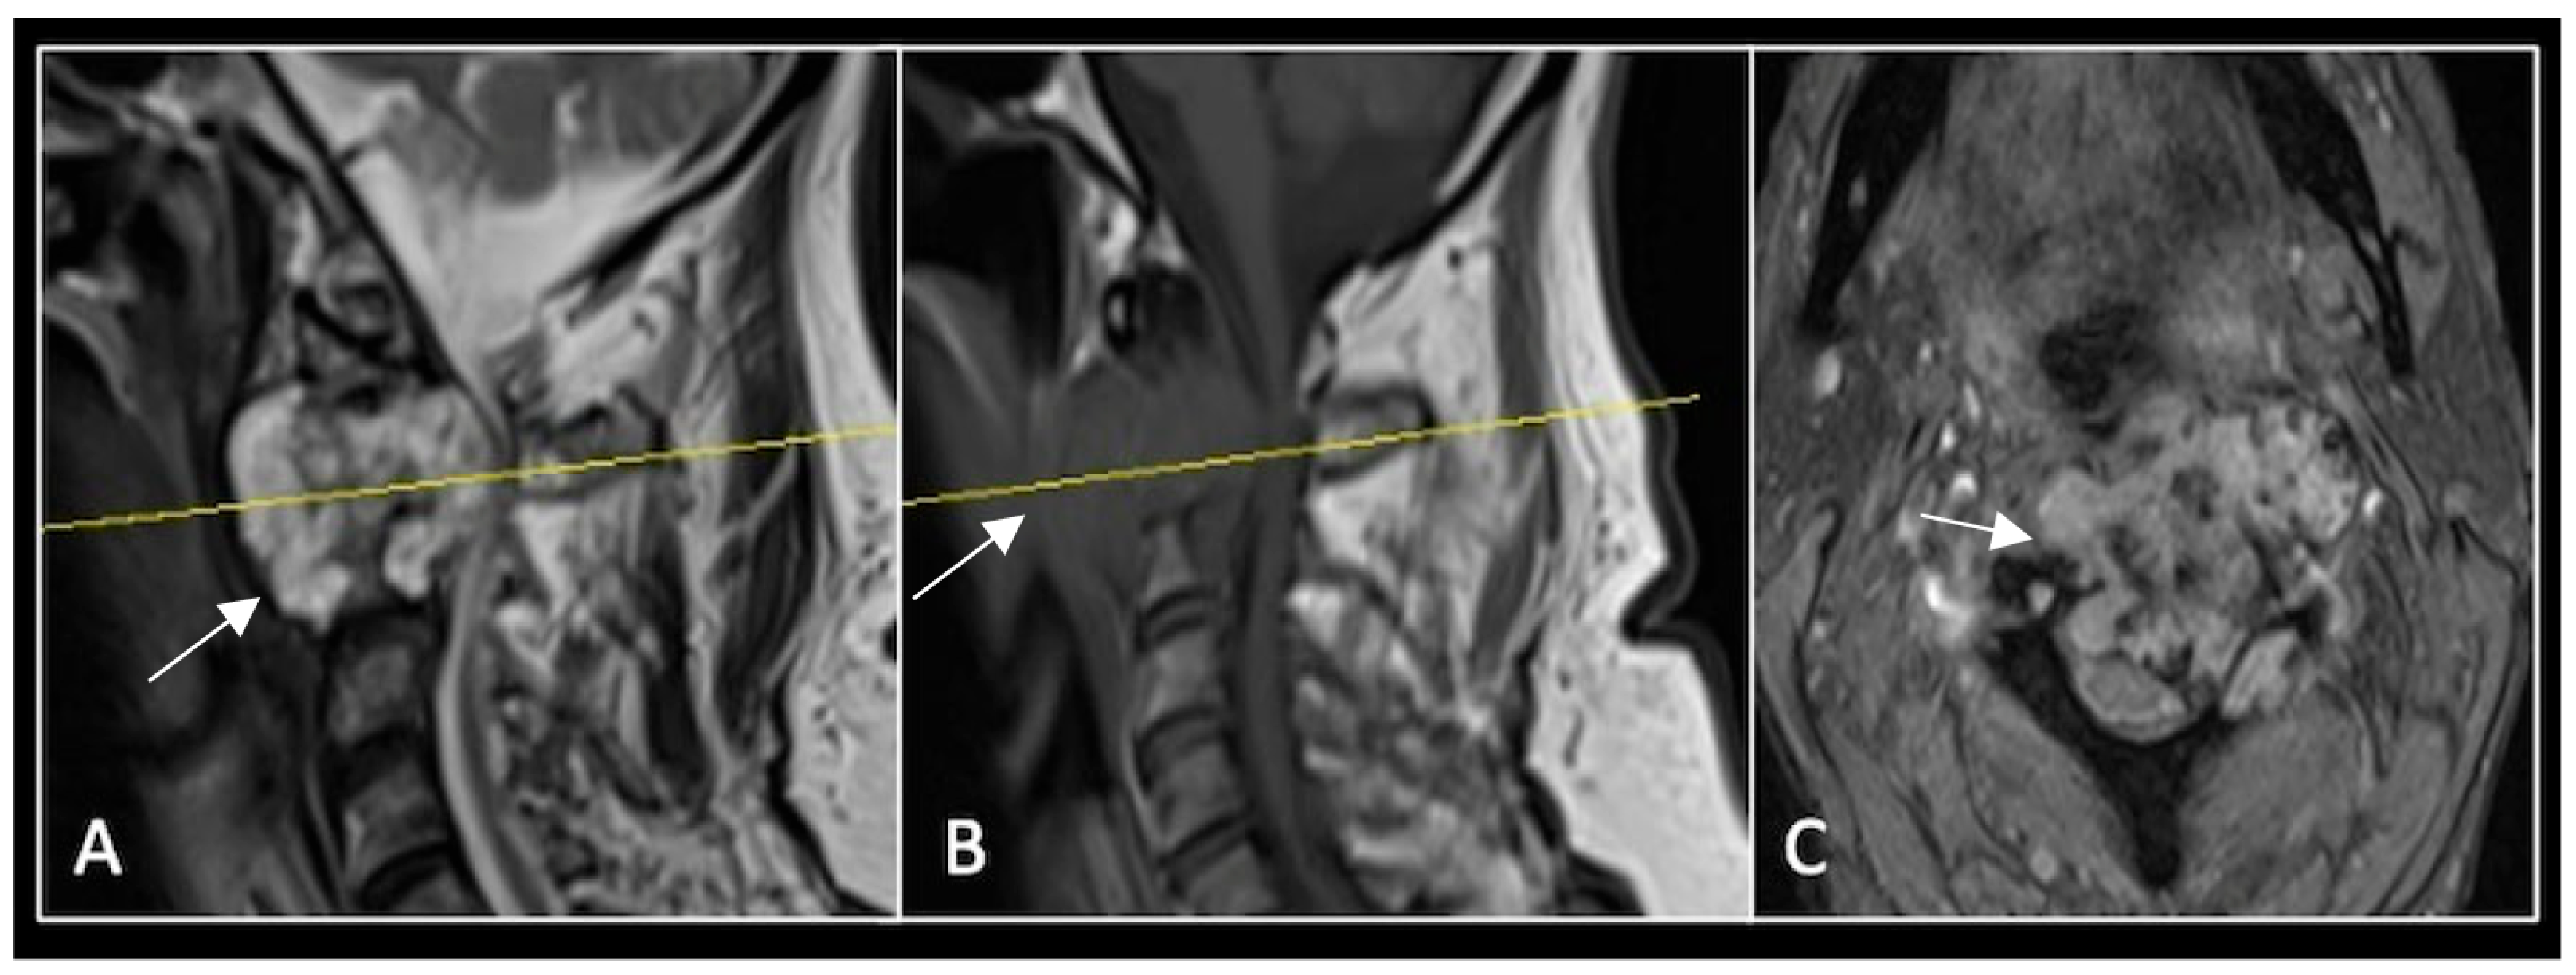

A 73-year-old male presented with an eight-month history of neck pain that was exacerbated on lying flat. He denied any symptoms of myelopathy and radiculopathy. He did not have any constitutional symptoms of malignancy. Past medical history included hypertension, renal cysts, and an ascending thoracic aneurysm. Examination was unremarkable. Diagnostic whole-spine MRI imaging demonstrated a large lobular mass localised to the cervical spine (Figure 2). Biopsy confirmed a conventional chordoma, and he underwent separation surgery followed by adjuvant proton beam therapy. Postoperative surveillance imaging at 12 months demonstrated stable disease (Figure 3).

Figure 2.

MRI demonstrating a destructive lobular lesion localised to the C2 vertebra (chordoma) (arrow). There is significant left-sided extension into the paravertebral tissues laterally and epidural space centrally with indentation of the cord. The yellow line on the sagittal images denotes the level at which the corresponding axial section was obtained. (A) T2-W sagittal; (B) T1W sagittal; (C) T2W axial.